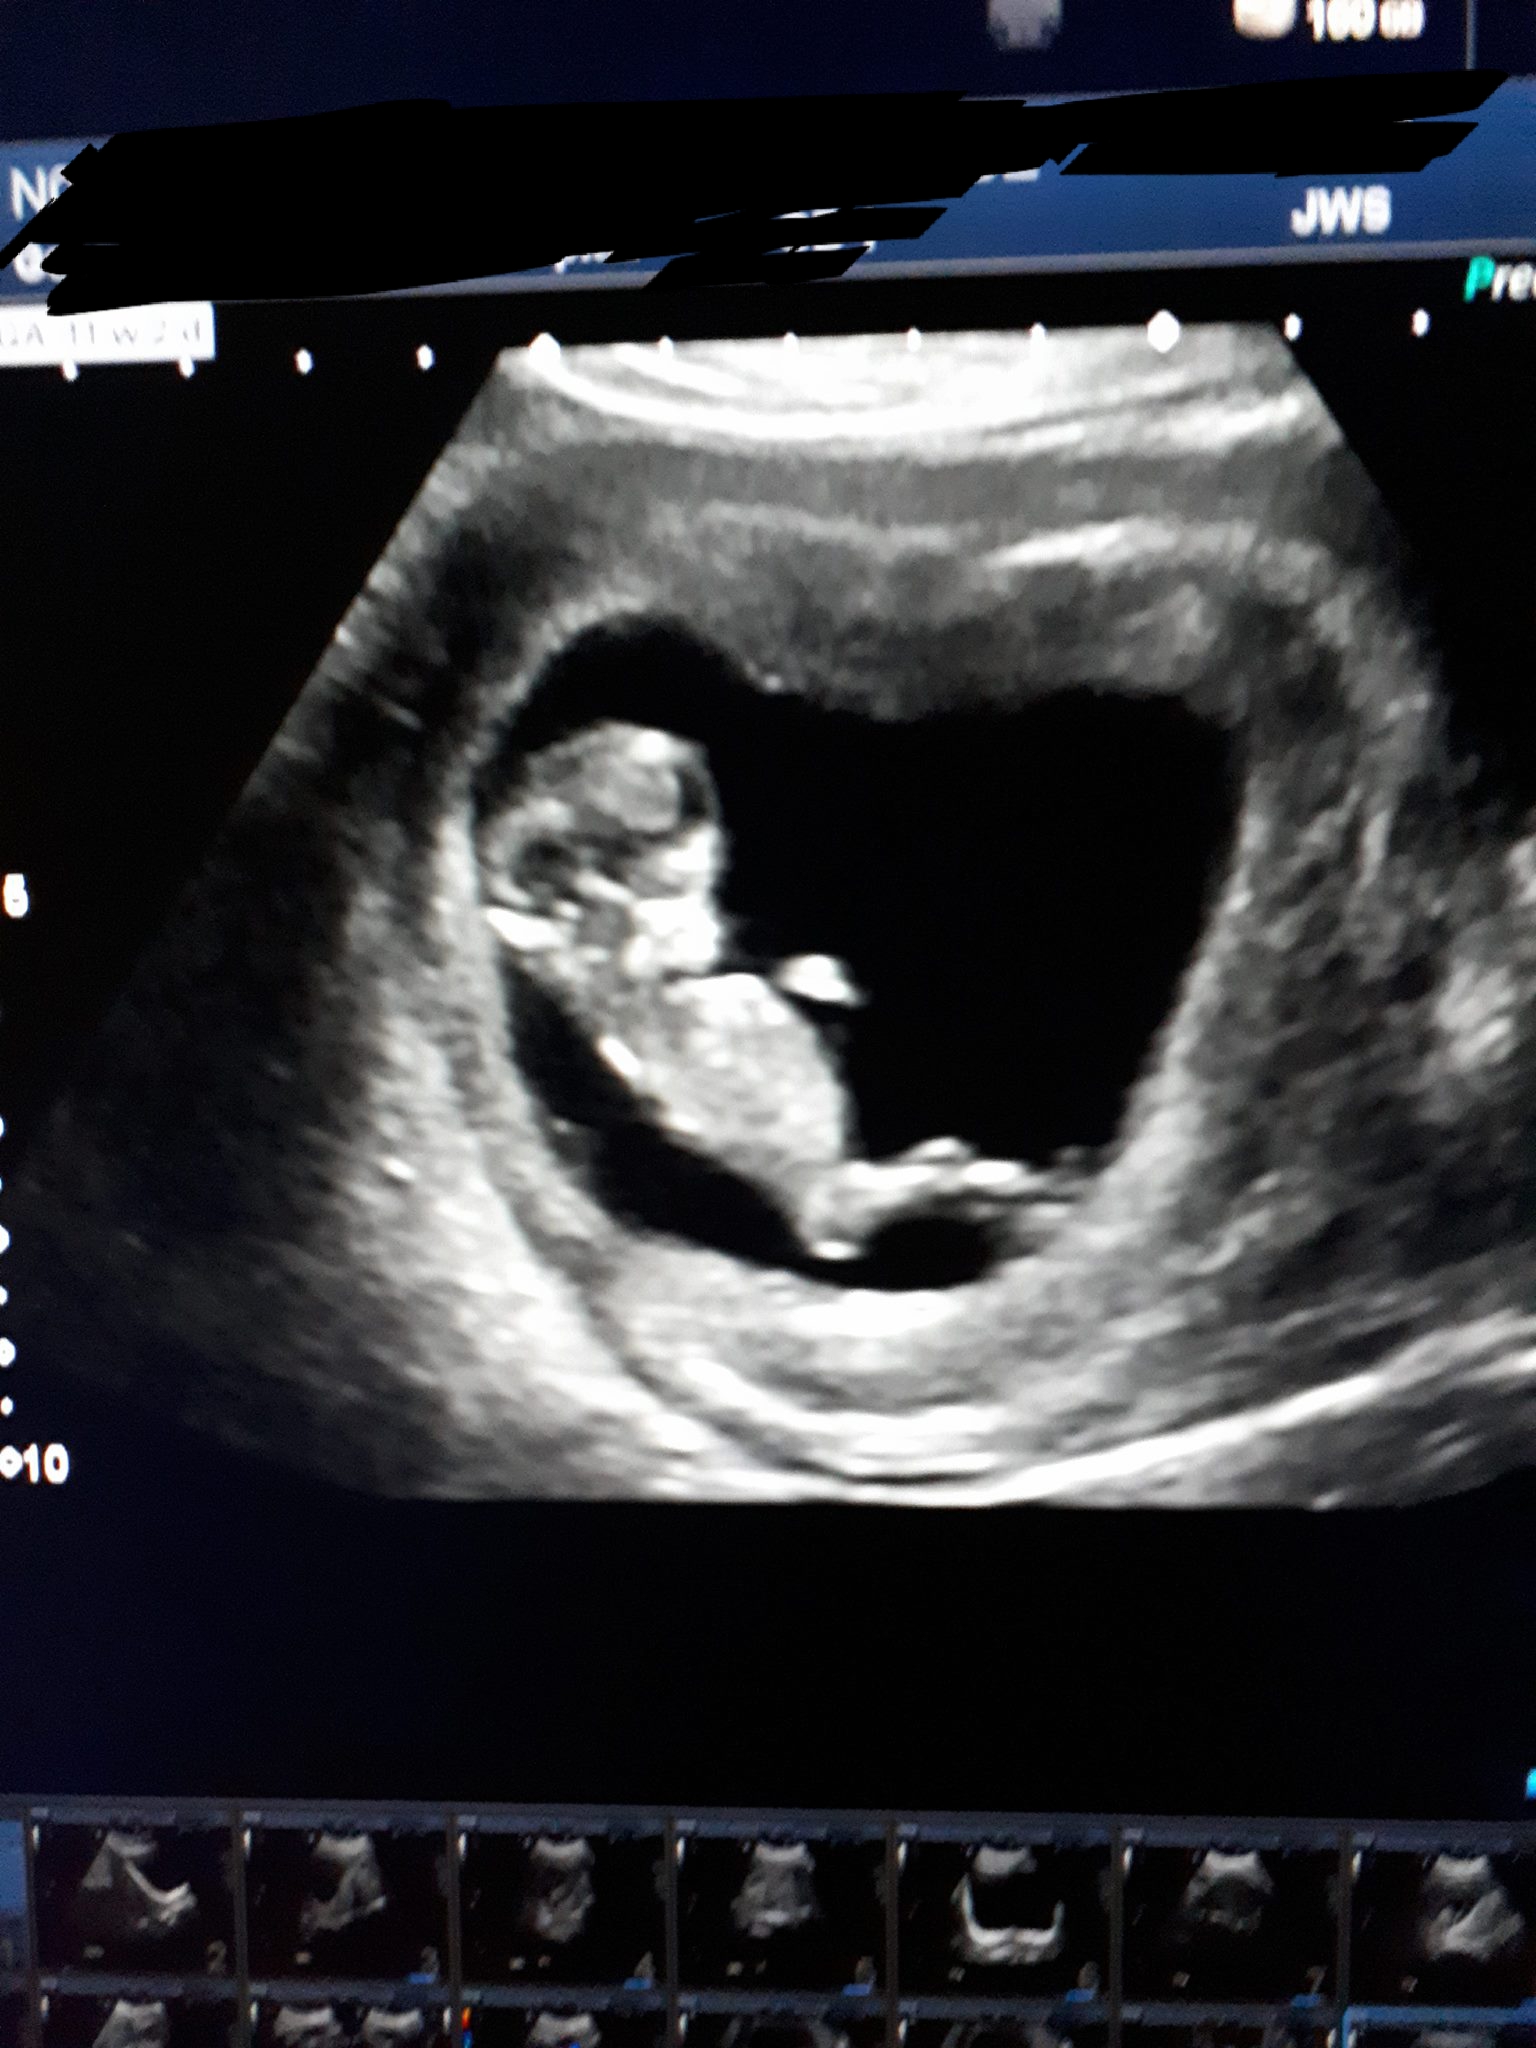

Attachment 38160Attachment 38161Attachment 38162

Ramzi has been debunked and 11 weeks is too early for a nub guess, sorry. If you happen to get a nub shot between 12-13 weeks, I'd be happy to guess!